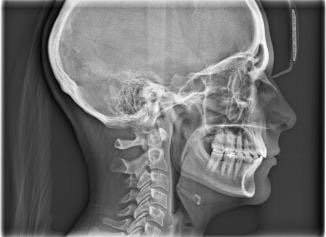

Lateral cephalometric

Purpose for lateral cephalometric

used to evaluate facial growth and development

ideal use for lateral cephalometric

For othrodontics practices or for children and adolescents